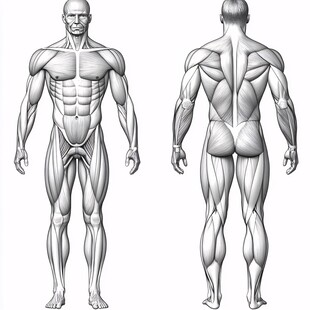

腰背部解剖图 非商作品

腰背部解剖图 非商作品 -

人体器官 商用作品

人体器官 商用作品 -

人体器官 商用作品

人体器官 商用作品 -

人体器官 商用作品

人体器官 商用作品 -